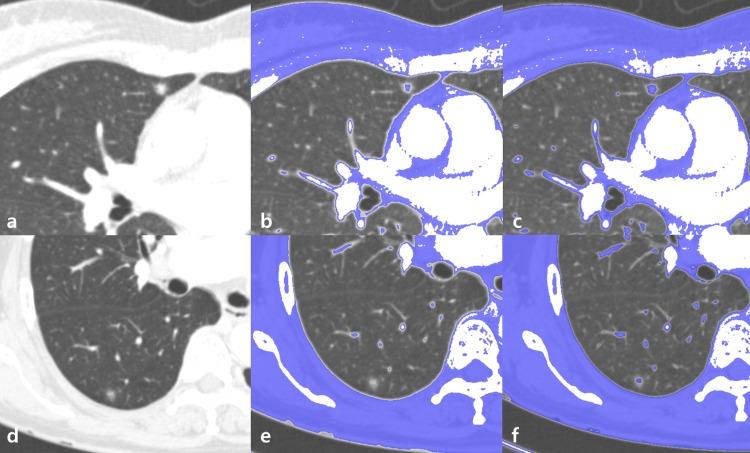

High versus low attenuation thresholds to determine the solid component of ground-glass opacity nodules.

Eighty-six pathologically confirmed GGNs < 3 cm observed in 86 patients (27 male, 59 female; mean age, 59.3 ± 11.0 years) between January 2013 and December 2015 were retrospectively included. The solid component of each GGN was defined using two different attenuation thresholds: high (-160 Hounsfield units [HU]) and low (-400 HU). According to the presence or absence of solid portions, each GGN was categorized as a pure GGN or part-solid GGN. Solid components were regarded as indicators of invasive foci, suggesting MIA or IA.